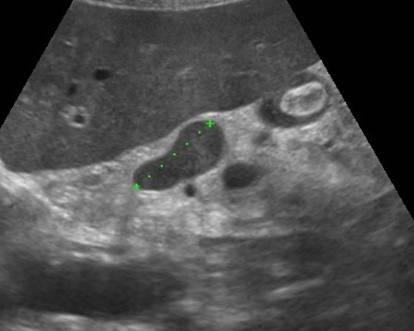

Мезентериальные лимфатические узлы: УЗИ и диагностика

Раздел: Лаборатория идей